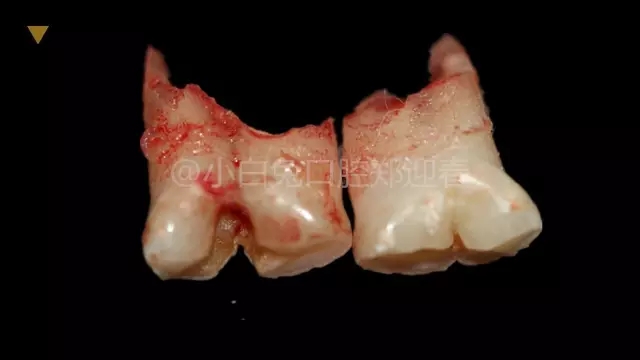

拔出后的離體牙

患兒,10歲,因上前牙未替換來診,查體:輕度反合,51和52、61和62均融合,且存在間隙約4mm,全面曲面斷層片顯示:11、21未萌,52、51、61、62牙根均有不同程度的生理性吸收。